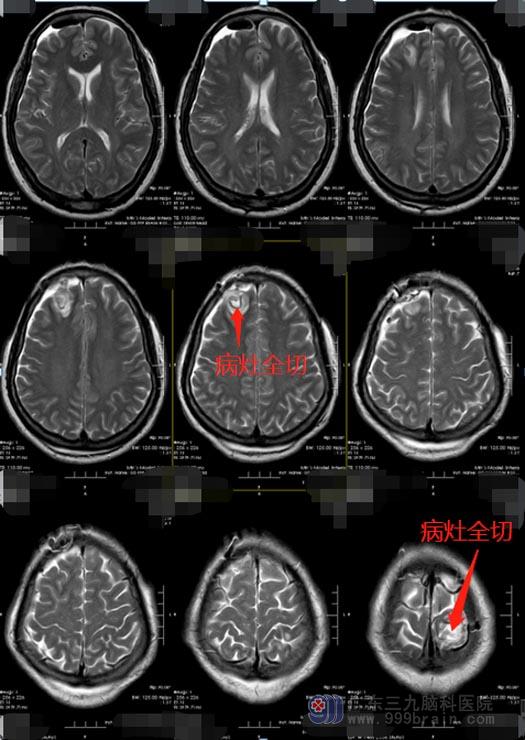

按照传统疗法,患者需要接受二次单独的开颅手术,才能逐一切除肿瘤。医院副院长、神经外五科主任鲁明带领团队在详细检查的基础上,精心制订手术方案,决定用一次手术机会同时切除颅内二处不同部位的不同病灶。家属知情同意后,由鲁明主刀在全麻下行“右额叶海绵状血管瘤及左顶部脑膜瘤切除术”,术中导航精准定位病灶范围,显微镜下将二个肿瘤顺利全切。

术后,林阿姨生命体征平稳,言语对答正确,肢体活动良好,没有遗留任何后遗症。